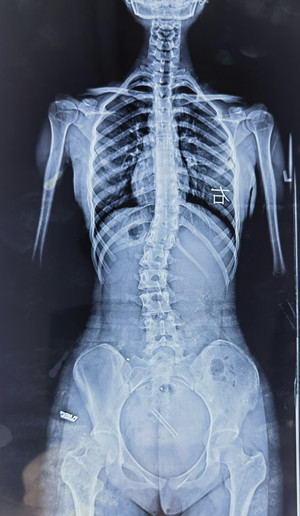

脊柱側(cè)彎拍X片

我的孩子可能脊柱側(cè)彎了,想拍一個(gè) “ 站立式全脊柱正側(cè)位X片 ” 。

您也可以給醫(yī)生看上圖,問(wèn)下醫(yī)生能不能拍這樣的X片(并不是所有醫(yī)院都有能力拍這樣的X片)。